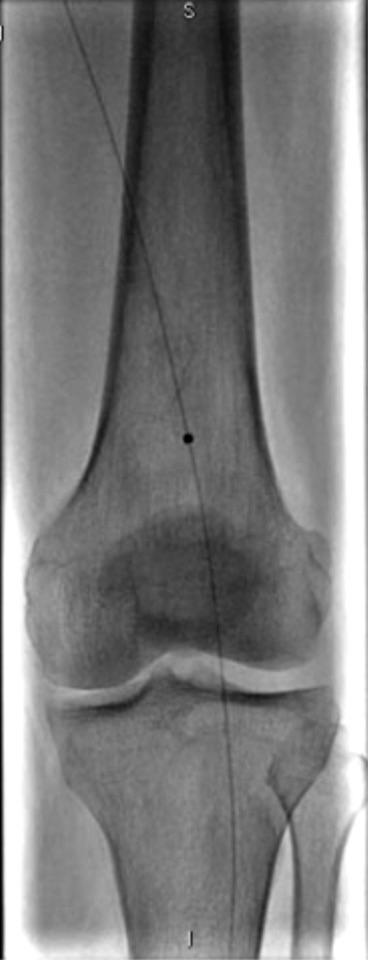

今天展示的病例是,老年男性,左下肢大腿血管堵掉了,下肢动脉cta的片子如下

患者和家属对于植入支架比较犹豫,要求尽量减少支架的植入。